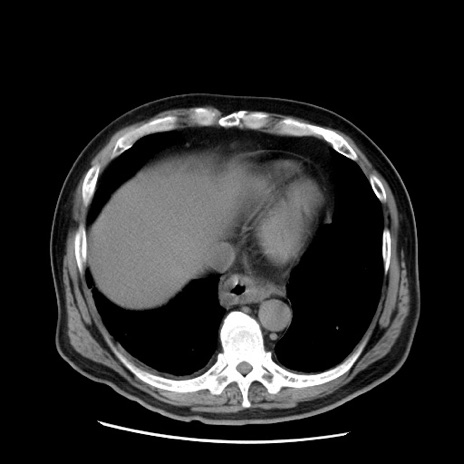

症例20(横断像)

【症例】 60歳代男性

【主訴】 腹部膨満、嘔吐

【現病歴】5日前頃より倦怠感を認め食事量減少し4日前の朝嘔吐、食事摂取困難となった。 3日前近医受診し点滴施行され整腸剤などを処方された。 当日他院を受診し、腹部膨満著明、炎症反応の上昇(CRP10.8、WBC11200)あり、紹介受診となる。

【身体所見】 意識JCS1 受け答えがはっきりしないBP 111/57mHg、 P 67bpm、、BT35.2°C、SpO2 97%(RA)、 腹部:膨隆、打診で鼓音あり、全体的に圧痛有り、腸蠕動音(-)、反跳痛ははっきりせず。

【データ】WBC 11400、CRP 14.20